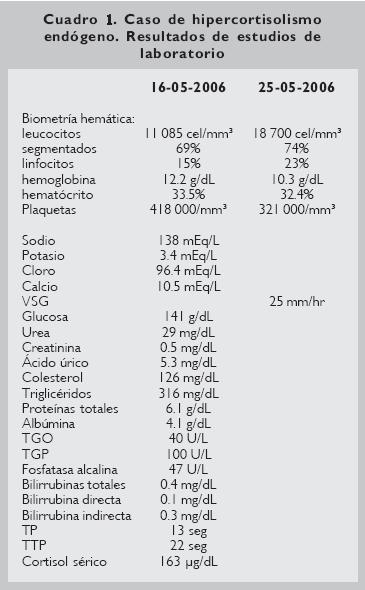

Por los datos clínicos, y el diagnostico de envío, entre otros estudios (Cuadro 1) se solicitó cortisol sérico, el cual se reportó en 163 ug/dL.

En el caso que nos ocupa se hicieron los siguientes exámenes: biometría hemática, prueba de función hepática, electrolitos, colesterol, triglicéridos, urea y creatinina, de los cuales los que se encontraron alterados fueron: glucosa de 141 mg/dL, triglicéridos con 316 mg/dL y cortisol sérico de 163 μg/dL.